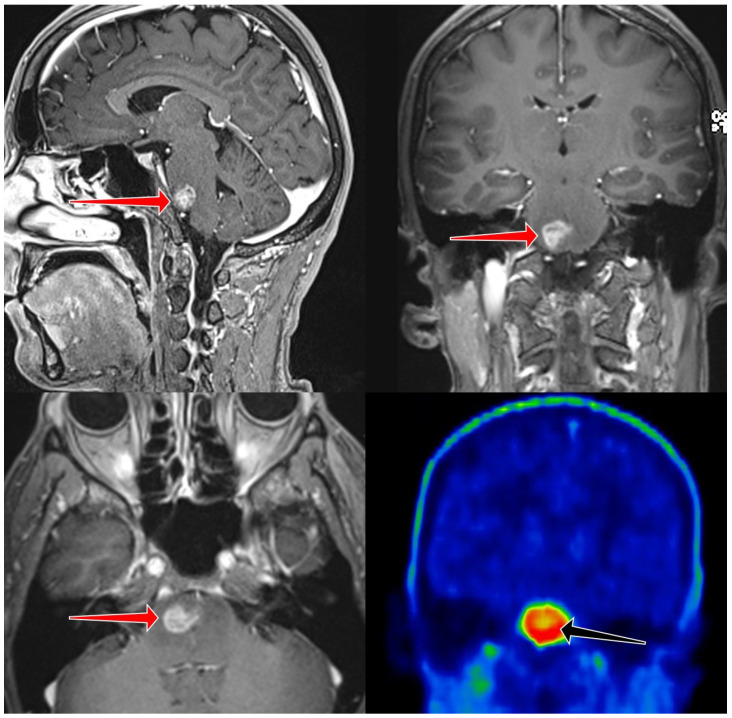

背景/目的:脑干胶质瘤的分类和分期有其自身的缺陷。手术活检仅在少数病例中可行。诊断主要依靠放射学特征。任何治疗都可能对生活质量产生重大影响;因此,正确和早期识别潜在的恶性病变是必不可少的,开始适当的治疗。氨基酸PET/CT与准确的代谢图谱可以帮助这一决策。方法:我们对2019年11月至2023年4月期间接受静态FET PET/CT检查的20例脑干病变不确定的患者进行了回顾性分析。我们使用多个肿瘤脑比(TBR)来评估显示长期和短期生存的患者亚组。结果:约登指数在TBR = 2.9时达到最大值。在此比率下,估计敏感性达到预期水平(91.7%),阳性和阴性预测值均处于良好的性能范围(68.8和75.0%),而特异性低于预期(37.5%)。结论:脑干胶质瘤的预后仍然具有挑战性。使用静态FET PET/CT可以更准确地检测高级别病变。在我们的分析中,我们发现TBR值为2.9最适合用于识别预后不良的患者。

Background/objectives: The classification and staging of brainstem glioma have its own pitfalls. Surgical biopsy is only possible in a small number of cases. Diagnosis relies mainly on radiological features. Any treatment may have a significant impact on quality of life; therefore, the correct and early identification of potentially malignant lesions is essential to initiate proper therapy. Amino acid PET/CT with accurate metabolic mapping can help in this decision-making.

Methods: We performed a retrospective analysis of 20 patients who underwent static FET PET/CT with uncertain brainstem lesions between November 2019 and April 2023. We used multiple tumor-to-brain ratios (TBR) to assess patient subgroups showing long-term and short-term survival.

Results: The maximum Youden index was reached at TBR = 2.9. With this ratio, the estimated sensitivity was at the desired level (91.7%), both positive and negative predictive values are in the good performance range (68.8 and 75.0%), while specificity was lower than expected (37.5%).

Conclusions: The prognosis of brainstem glioma remains challenging. The use of static FET PET/CT results in more accurate detection of high-grade lesions. In our analysis, we found a TBR value of 2.9 to be the most appropriate for identifying patients with a poor prognosis.